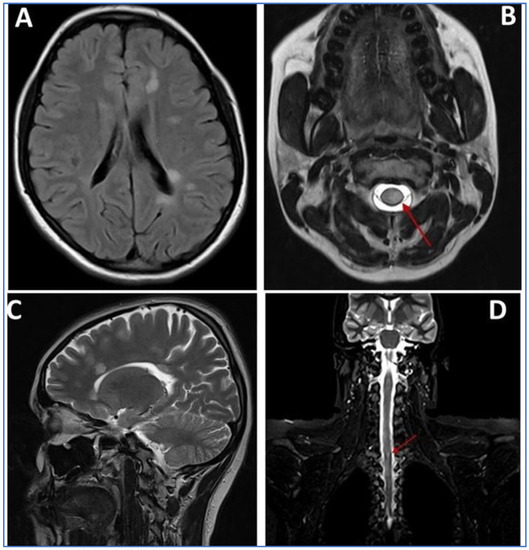

A 40-year-old female patient reported to the King Abdulaziz University, Faculty of Dentistry/University Dental Hospital (KAU-FD/UDH), with the relapsing–remitting type of MS diagnosed in the year 2020 (Figure 2A–D). She was complaining of bleeding gums with a burning sensation, halitosis, and inability to brush due to pain.

Figure 2. MRI scan images (AD): (A) axial T2-weighted FLAIR MRI through the brain at the level of the ventricles showing multiple well-defined foci of increased signal intensity seen adjacent to left posterior aspect of periventricular white matter; (B) fat-suppressed axial T2-weighted MRI showing lesion around the spinal cord (Red Arrow); (C) sagittal T2-weighted MRI through the brain at the level of the ventricles showing multiple well-defined foci of increased signal intensity seen adjacent to the anterior aspect of periventricular white matter; (D) coronal T2-weighted MRI through the spinal cord showing well-defined foci of increased signal intensity (Red Arrow).